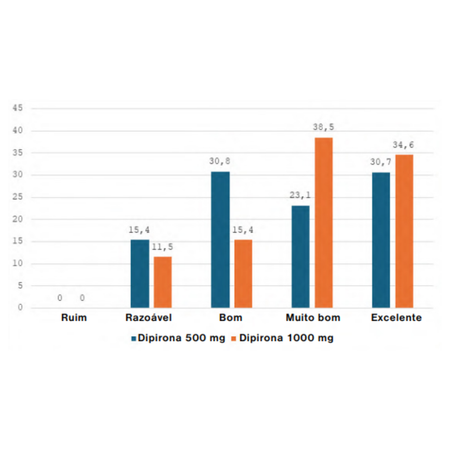

Objetivo: O objetivo desse estudo foi avaliar se há benefício em aumentar a dose da dipirona 500mg para 1.000mg quando coadministrada com a nimesulida, em cirurgia de terceiros molares inferiores. Métodos: Foi realizado um ensaio clínico randomizado, de amostras dependentes, triplo-cego, pelo método split-mouth. Os pacientes foram submetidos a dois procedimentos em tempos distintos, e receberam as medicações após randomização e alocação em: grupo A (dipirona 500mg + nimesulida...

Objective: The aim of this study was to assess whether there is a benefit in increasing the dose of dipyrone from 500mg to 1,000mg when co-administered with nimesulide, in lower third molar surgery. Methods: A randomized clinical trial of dependent samples, triple-blind, was carried out using the split-mouth method. The patients underwent two procedures at different times, and received the medications after randomization and allocation into: group A (dipyrone 500mg + nimesulide 100mg) or...